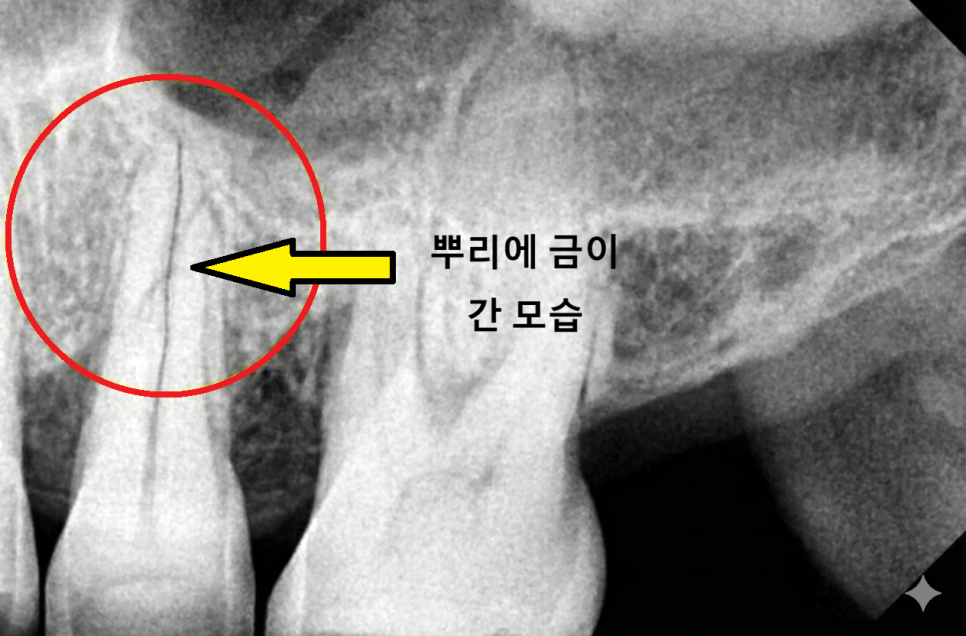

만약 증상을 방치해서 균열이

치아 뿌리라는 깊은 부분까지

진행된다면 어떻게 될까요?

뿌리가 쪼개지면

세균 침투를 막을 방법이 없어

안타깝게도 치아를 살리지 못하고

발치를 해야 하는 상황에 이를 수 있습니다.